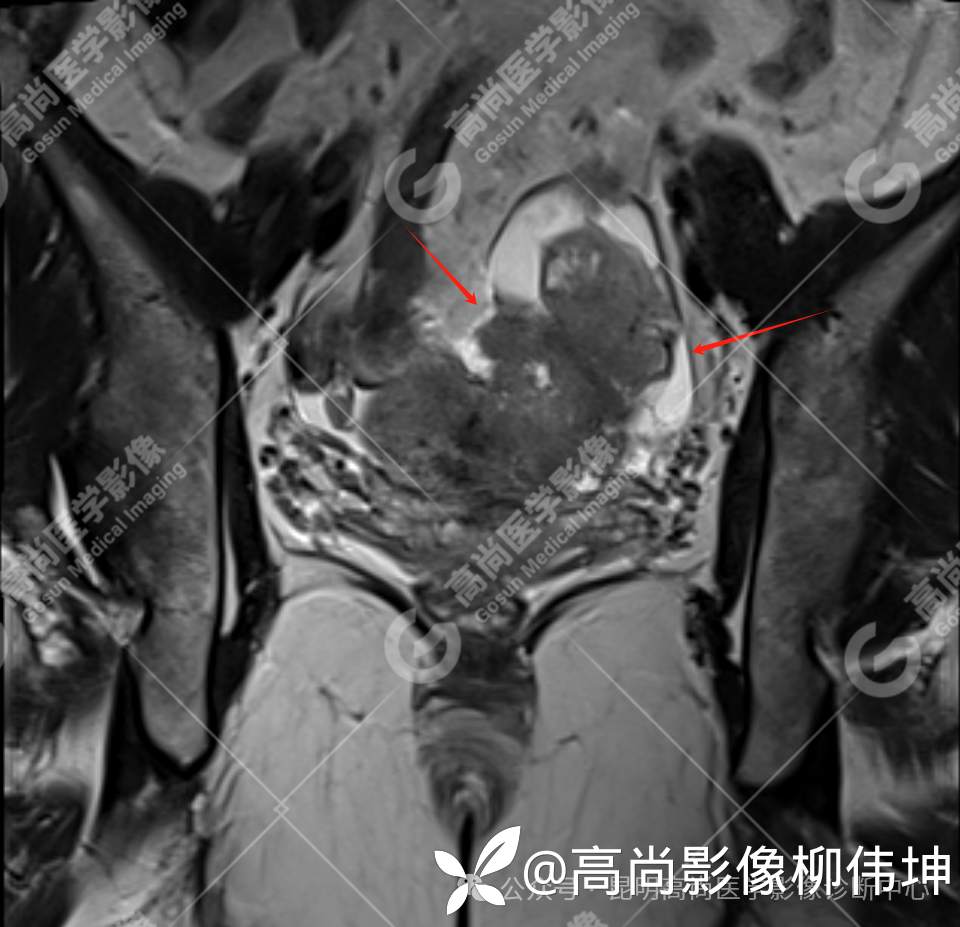

T2WI-cor

(2)MRI表现:通常双侧发生,体积巨大,呈外生性、囊实性、乳头状生长,其内见大量长T1长T2液性信号影及线性分隔,囊壁厚薄不均,可见壁结节及不同比例实性成分,呈T1等信号,T2略高信号。扩散受限,DWI呈高信号,ADC呈低信号。增强扫描实性成明显强化。另外,常可检出腹水、腹膜增厚、盆壁及盆腔脏器受累、淋巴结肿大等表现。